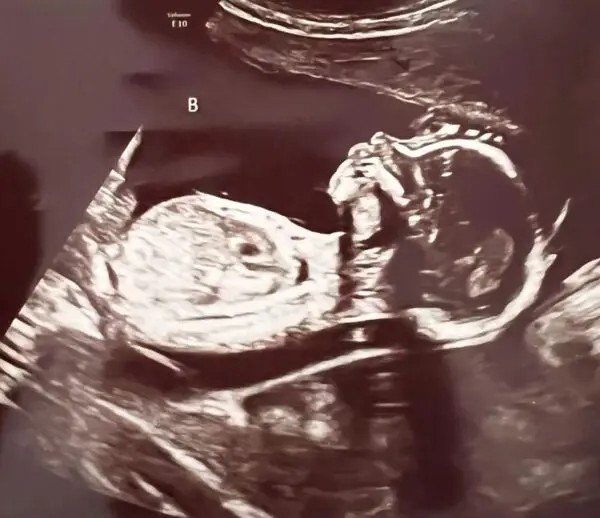

When Ashley had an ultrasound two weeks later and learned that she was expecting not one, but four babies, her joy quickly turned to shock.

The fact that the expecting woman, who already has a daughter from a previous relationship, learned that the four kids are actually two sets of identical twins rather than quadruplets astonished even her ultrasound technician.

She wrote “A, B” on the screen when she first started the scan, which caused her to stop and look at her and say, “Wait, I’m having twins?” she recounted to Good Morning America.

According to Ashley, the ultrasound technician was so perplexed by what she saw that she had to leave the room to determine whether such a thing was actually feasible.